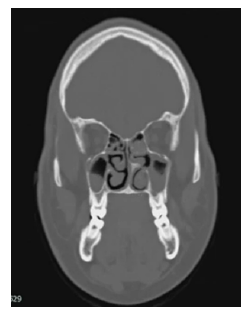

Furthermore, CAT scans of the thorax, neck, PNS and abdomen were performed that same day, revealing multiple bilateral axillary lymphadenopathies (Figure 2), suspicious malignant lymph nodes in the neck, mucosal thickening and opacification of ethmoidal and bilateral maxillary PNS cells with gas bubbles, obstruction of the osteomeatal complex (Figure 3), splenomegaly, and retroperitoneal lymphadenopathies.

Computed axial tomography of paranasal sinuses, coronal plane in bony window, showing bilateral invasion by soft tissue material in bilateral maxillary and ethmoidal paranasal sinuses.

Figure 3: Computed axial tomography of paranasal sinuses, coronal plane in bony window, showing bilateral invasion by soft tissue material in bilateral maxillary and ethmoidal paranasal sinuses.

Source: Image obtained while conducting the study.